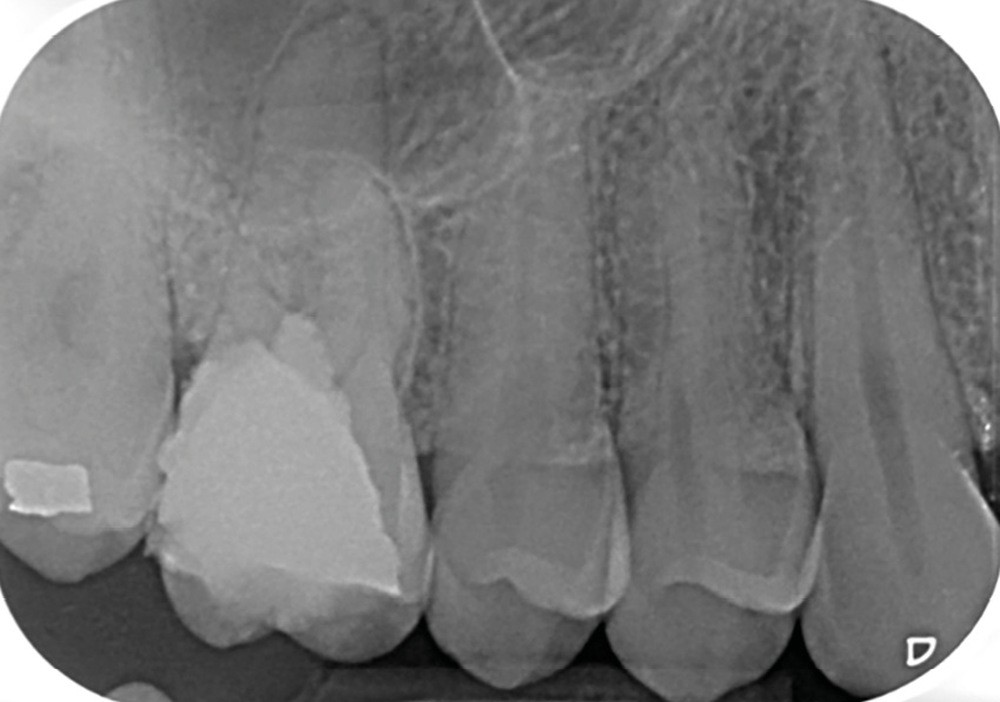

Perforation supra-osseuse (fig. 1)

Les perforations supra-crestales sont la plupart du temps iatrogéniques et surviennent lors de la réalisation de la cavité d’accès, ou de la recherche des entrées canalaires. Il s’agit généralement d’une communication avec un diamètre bien défini et aux contours nets. De ce fait, ce type de perforation est appelée « perforation à quatre parois ». Les perforations peuvent également être d’origine pathologique (résorption cervicale externe, carie active).